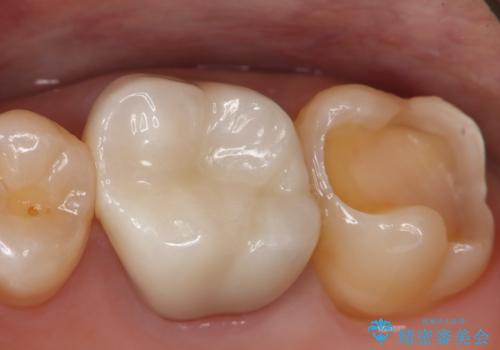

銀歯を白くしたい セラミックインレー

- 左上7番の銀歯をセラミックにやり変え希望の患者様です。

切削量・形態からセラミックインレーでの治療を計画しました。

銀歯とその直下のう蝕を除去した後、CRにて裏層しています。

インレー装着の際はラバーダムを使用しています。